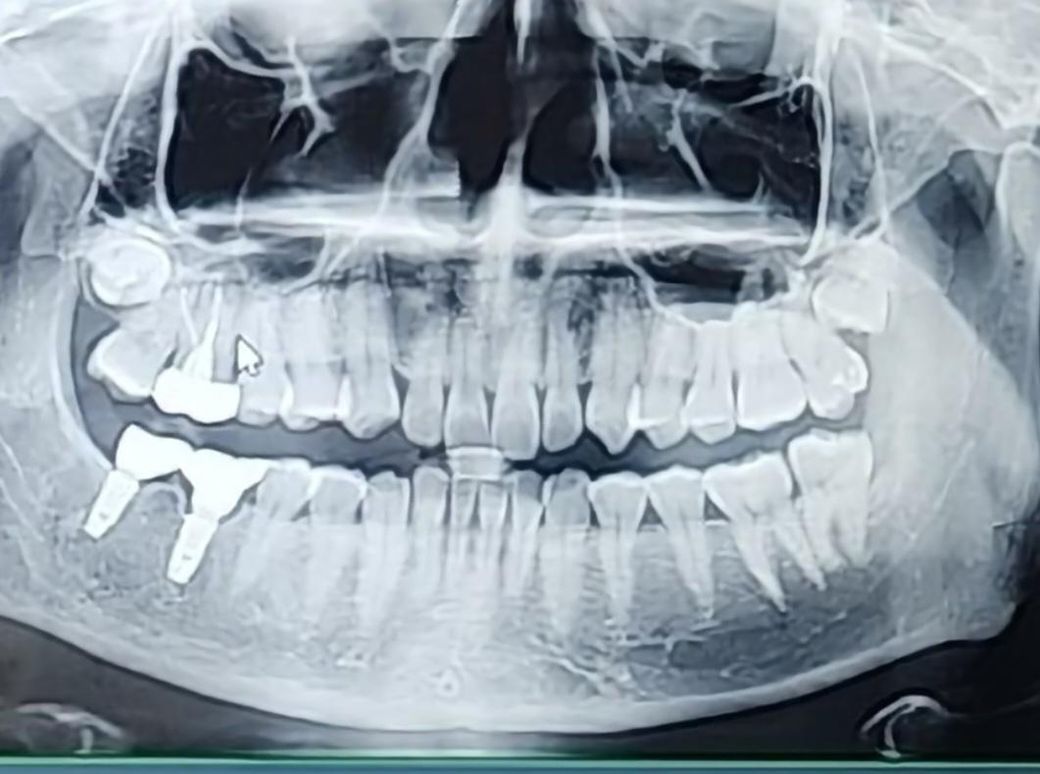

사랑니를 빼야할지 알려주세요 매복인것

매복 사랑니 같은데 빼야할까요? 유튜브보니 어쩌피 사랑니는 빼야하고 나이들면 들수록 뺄 때 아프다고 하네요 이참에 빼려는데 제 사랑니 어떤가요?

사진상에 보이는 위쪽 매복사랑니는 별다른 문제가 없다면 발치를 안하셔도 크게 문제가 되진 않을것같습니다.

위치가 뼈 안쪽이고 인접 어금니와의 위치관계상 발치 난이도가 쉽지는 않습니다. 나이들면 점차 사랑니가 잇몸뼈와 유착되어 빼기 어려워지는 건데, 어차피 지금 사랑니는 발치 난이도가 높습니다.